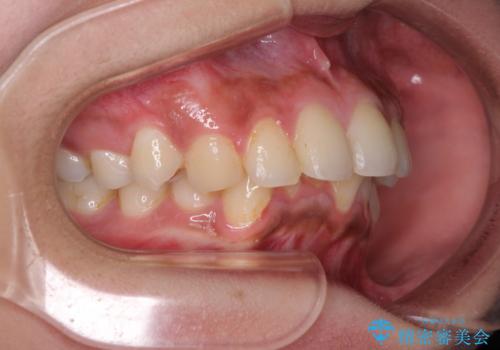

深い咬み合わせと前歯のデコボコ インビザラインによる矯正治療

- 前歯のデコボコと、食いしばりやすい咬み合わせを気にして来院された患者様です。

骨格的に下顎骨が左側に偏位しており、インビザラインでの矯正治療では奥歯の咬みにくさが残る仕上がりが懸念されましたが、新幹線での通院となるため、来院回数の少ないインビザラインでの治療を希望されました。

リスクをご説明した上で、インビザラインにより気になっている叢生と深い咬み合わせを改善していくこととしました。

治療途中では、左右ともに奥歯が咬みにくい状態が続き、問題なく噛めるようになるまでに長期間を要しました。

一方で、デコボコや下顎の前歯が隠れてしまうほどの深い咬み合わせはしっかりと改善されました。